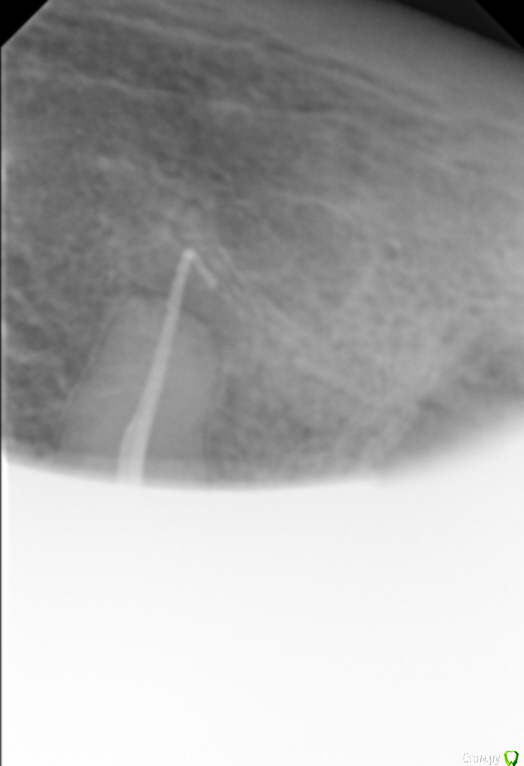

Елена509 Опубликовано 19 ноября, 2015 Поделиться Опубликовано 19 ноября, 2015 Доктора, помогите, пжл, ситуация какая - ортопед направил для удаления штифта и перепломбирования к.к 35, начали - анестезия, выудили штифт, начали расширять, уперлись на 15 мм, пошли на снимок с гутт штифтом(прилагается), недолет, вернулись, сразу прошли дальше, по апексу -18мм, убавила до 17,5, мастер штифт - 35, латералка, пошли на контроль, а там - загнутый штифт за верхушкой(рг прилагается), вернулись, все вытащила, загнутый тоже(95% - я его прям признала), отмыли просушили, по апексу те же 18мм, примеряю мастер штифты все как то не так встает, в итоге 70 подогнала, на те же 17,5 мм, поставила, с латералкой, идем на контроль, там вот такая вот фигня(рг - "последний"), вопросы - это что, невытащеннный гут.штифт или на его место эпоксидка затекла? что с прогнозом и что делать? 1 Ссылка на комментарий

Сева северный Опубликовано 19 ноября, 2015 Поделиться Опубликовано 19 ноября, 2015 (изменено) перед тем, как пошли делать с гут.штифтом рг недолет показывал, вроде нормально все было, когда пломбировали, штифты тоже никуда не уходили на месте стояли, я даже как то растерялась сильно, когда на контрольном на столько за апекс ушлисудя по фото....зуб резарцинен..... с дефектом твердых тканей( это диазноз)..ферол наверное отсутствует. Чтобы было понятно ......лечение резарциненого зуба с таким разрушением..+ осложненным необходимостью эндолечения .... является альтернативой удалению.Что касается :Что за верхушкой ?.... Границы четкие, если вынули гуту ....крючком.... для себя считайте силер..даже если и гута связь с каналом зуба отсутствует. поэтому реакция будет либо незначительная , либо отсутствовать вообще. Прогноз по зубу, строил бы из ортопедической целесообразности.... Изменено 19 ноября, 2015 пользователем Сева северный 1 Ссылка на комментарий

Л Ю С Я Опубликовано 20 ноября, 2015 Поделиться Опубликовано 20 ноября, 2015 Здесь явная резорбция апекса, поэтому локатор мог показывать неправильно. В таких случаях делайте снимок с финишным файлом, где он? Ориентируйтесь больше на рентгенологическую длину, после лечения может произойти ещё небольшая убыль апекса, поэтому пакуйте -0,5, лучше мта. Какой билдап планируется в зубе? И вообще надо рассматривать картину восстановления окклюзии в целом 1 Ссылка на комментарий

Sampson Опубликовано 21 ноября, 2015 Поделиться Опубликовано 21 ноября, 2015 Резорциненный+пародонтитный+ изменения апекальной трети корня+ тень материала за верхушкой = Я бы зуб пока сохранил в целях наблюдения. и раз в неделю проводил перкуссию. При положительной динамике отправил к ортопеду. При отрицательной к хирургу. Ссылка на комментарий